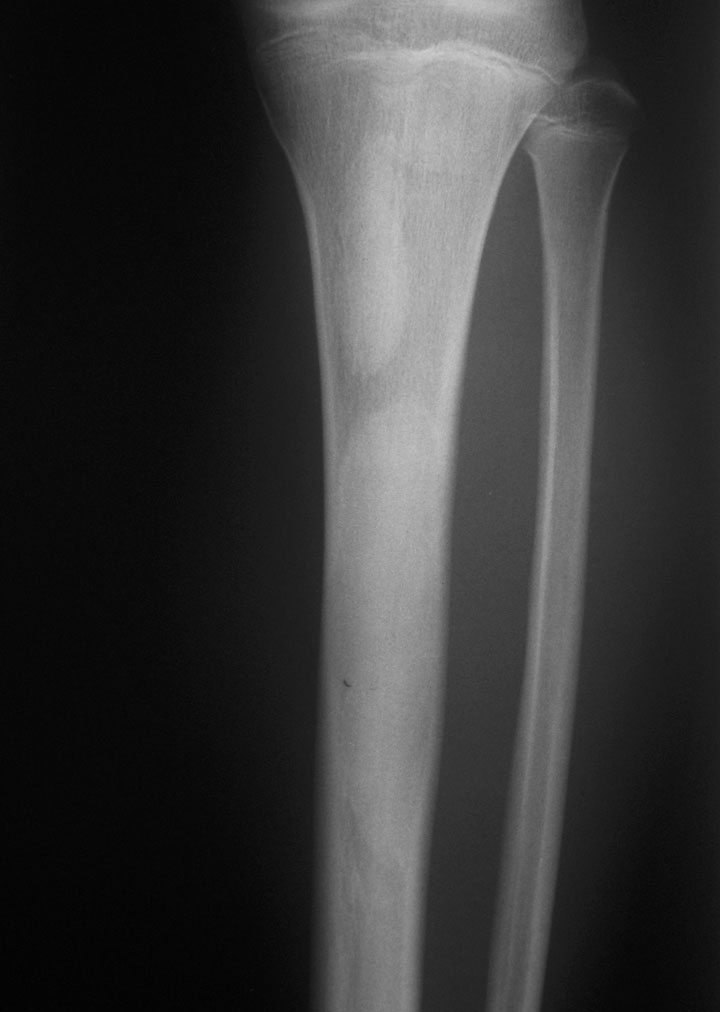

标题: CT19885:左胫骨上端肿瘤。 [打印本页]

标题: CT19885:左胫骨上端肿瘤。

男,20岁,医学院学生,11年前感左胫骨上端劳累后酸痛,曾由父母带到国内好几家有名望的医院诊治,但众说不一,所以基本上没有治疗。今年三月又开始出现症状,又到多家省级医院求治,但专家们的意见还是不能统一。各生化检查正常。mri考虑到胫骨上端良性血管瘤可能性大。ct考虑纤维瘤可能性大。请各位发表高见。

考虑胫骨多发性内生骨瘤。

胫骨多发性内生骨瘤可能。

考虑纤维类肿瘤,以骨化性纤维瘤可能性大。

考虑左胫骨良性骨肿瘤或骨肿瘤样病变(多发性内生骨瘤?骨纤维结构不良?)。

考虑胫骨多发性内生骨瘤可能。应该传骨窗。

左胫骨良性肿瘤或肿瘤样病变。骨纤?

考虑左胫骨良性骨肿瘤或骨肿瘤样病变(多发性内生骨瘤?骨纤维结构不良?)。骨梗死,纤维瘤。